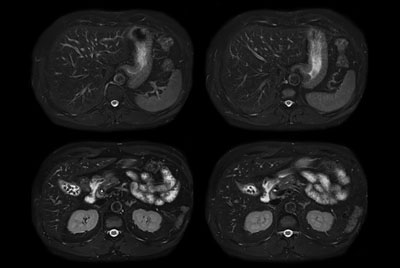

SmartSpeed Liver

Comprehensive Liver exam of focal liver lesions

Comprehensive Liver imaging at 3.0T

Comprehensive Liver imaging at 1.5T